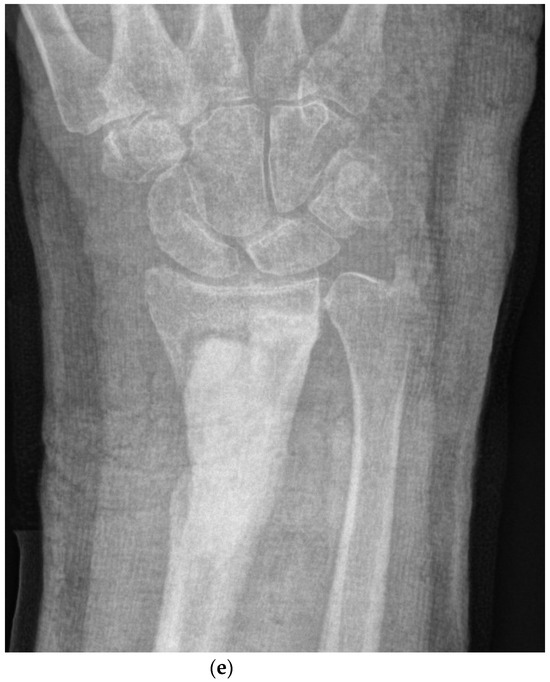

All patients were treated with a single-stage protocol incorporating deep tissue sampling, excision of dead and compromised tissue, management of the excised dead space, bone stabilization (if required) and soft tissue closure, as previously described [32] (Figure 2a–e).

Figure 2.

(a). The surgical management with implantation of a gentamicin-loaded antibiotic carrier. This 32-year-old woman suffered a closed fracture of her distal radius in a fall. After fixation with a plate, the fracture became infected. The plate was removed, but she continued with a draining sinus and active infection. This preoperative radiograph shows the dead bone in the radial metaphysis (white arrow), but the fracture has healed. (b). The magnetic resonance scan demonstrates the area of high signal around the dead bone, with active infection. (c). At operation, the volar aspect of the wrist was opened and the infected bone exposed. Five deep tissue samples were taken for microbiology and three for histology. The central area of necrotic bone and infected tissue (white arrow) was excised back to healthy bleeding bone. (d). The excised dead space has been filled with CERAMENT G (with gentamicin), completely filling the bone defect. The material was compressed into the bone and the skin closed in layers. (e). The postoperative radiograph shows the antibiotic carrier in place, filling the defect.